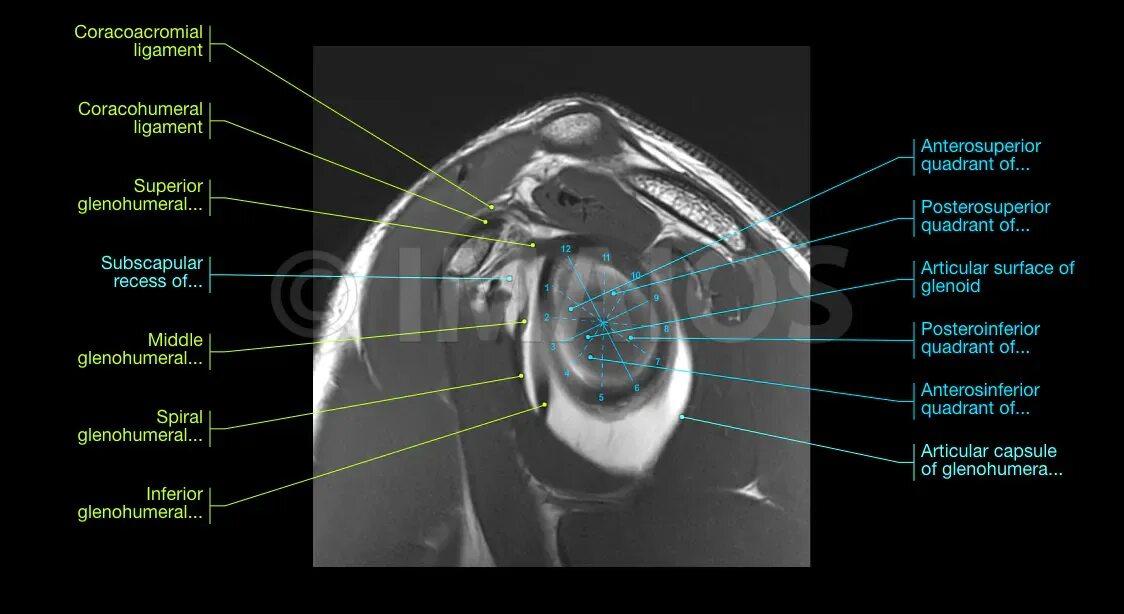

Изменение фиброзной губы гленоида